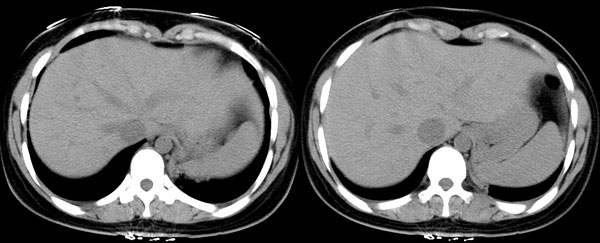

女性,25岁。反复咯血3年,再咯10天。外院x线胸片示:肺炎?支扩?

ct所见:左肺下叶基底段见大片状毛玻璃样改变,其内可见扩张细支气管。

ct诊断:考虑支气管扩张合并感染.

ct所见:左肺下叶基底段见大片状毛玻璃样改变,其内可见扩张细支气管及血管纹理影。后接正常描述。

ct诊断:左肺下叶支气管扩张伴出血。

胸部ct平扫所见:胸廓两侧欠对称,左侧略小,胸壁骨质结构完整。左肺下叶后、外基底段

见大片状毛玻璃样淡薄影,边缘渐淡,其内可见多个环形小囊状影。余肺野清晰,

肺纹理规则,气管支气管通畅,内壁光滑。心脏、大血管大小、形态、密度未见

明显异常,胸膜不厚、光滑,纵隔内未见明显肿大淋巴结。

诊断意见:左肺下叶大片状毛玻璃样淡薄影考虑支气管扩张伴出血。